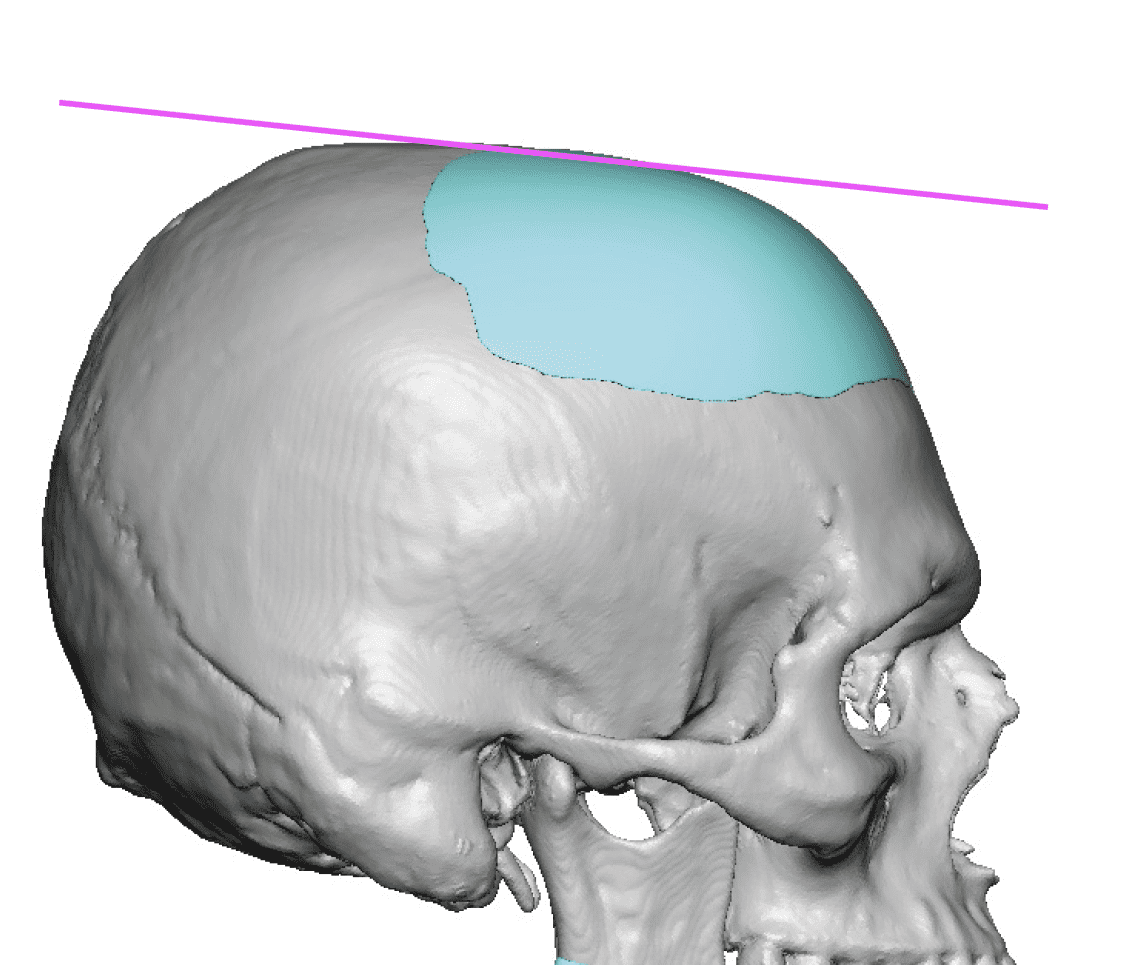

Desire for further skull augmentation after a primary skull implant.

Five years after an initial custom skull implant placement a new custom skull implant that increased the volume by 35% was placed.

Desire for further skull augmentation after a primary skull implant.

Five years after an initial custom skull implant placement a new custom skull implant that increased the volume by 35% was placed.